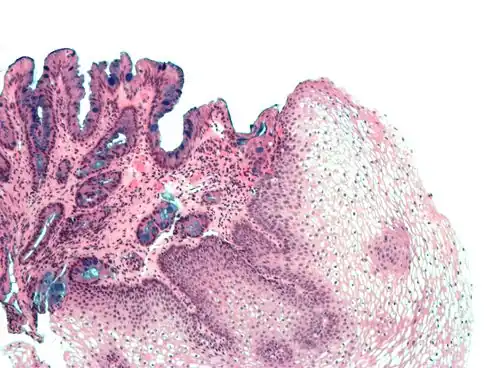

Non-keratinized stratified squamous epithelium, image highlights the epithelial nucleuses, rest of the epithelial layer, underlying connective tissue and other epithelia